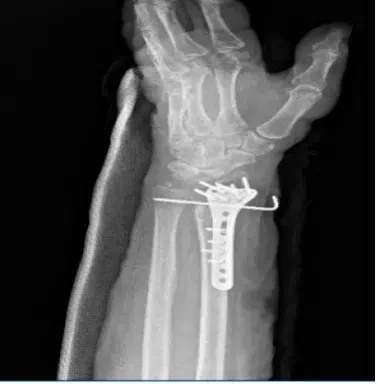

El médico revisó y discutió las radiografías; el paciente se encuentra en estado post-ORIF fractura del radio distal y del proceso estiloide cubital. El hardware quirúrgico está instalado en el radio distal. Hay un alfiler de fijación que se extiende a lo largo del radio distal y el cúbito. Los fragmentos de fractura aparecen en una posición y alineación satisfactorias.

Vistas de radiografía de la muñeca izquierda 2